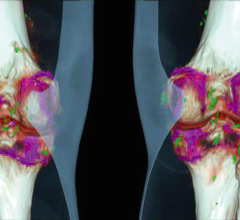

The FDA has cleared Siemens' syngo.CT Single Source Dual Energy software package, that enables spectral imaging using which is designed to operate with CT images acquired with Siemens single source CT scanners.